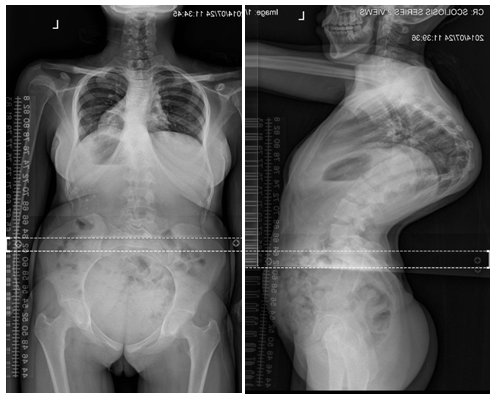

Antero-Posterior and lateral view radiographs showed a severe thoracic kyphosis of 135° from T7-T12 and a lumbar lordosis of 111° (Figure 4 & 5).

Figure 4 Full Spine Antero-Posterior.

Figure 5 Full Spine Lateral Radiograph Radiograph.